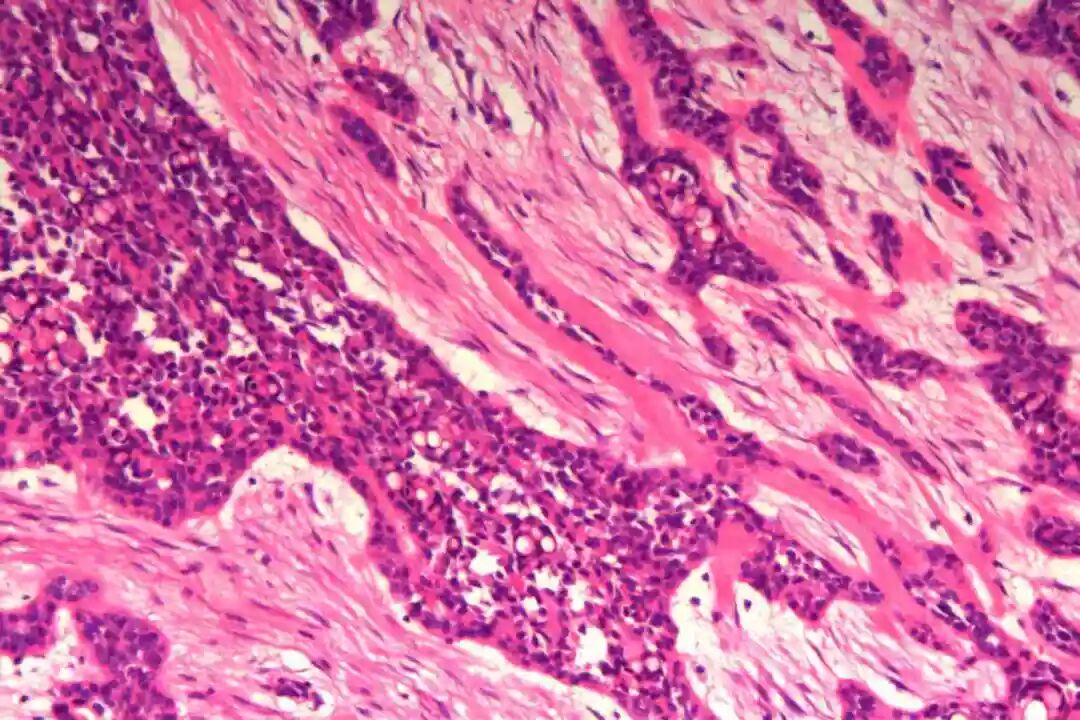

细胞形态:基底样肌上皮细胞体积较小,呈圆形或卵圆形,细胞核深染、染色质均匀,核仁不明显,胞质稀少、淡嗜酸性;腺上皮细胞体积略大,呈柱状或立方状,细胞核淡染、染色质疏松,核仁清晰,胞质丰富、嗜酸性。实性巢团内可见少量微小腔隙,腔隙内可含有少量嗜酸性或嗜碱性黏液样物质(PAS染色阳性),这是实体型与其他实性肿瘤的重要鉴别点;核分裂象少见,一般≤5个/10HPF,部分实体型区域可出现轻度至中度细胞异型性,但无明显恶性增殖活性表现,与高级别乳腺癌的细胞异型性有明显区别。

实体型区域与经典型区域无明显明确界限,相互穿插分布,实体型巢团可逐渐过渡为经典型的筛状或管状结构,两种区域的细胞成分相互延续,均可见腺上皮细胞与肌上皮细胞的混合存在,无明显细胞异型性差异(实体型区域异型性略高于经典型,但整体温和)。这种混合性形态是本病的重要镜下特点,也是与单纯实体型PACC、单纯经典型PACC的主要区别。